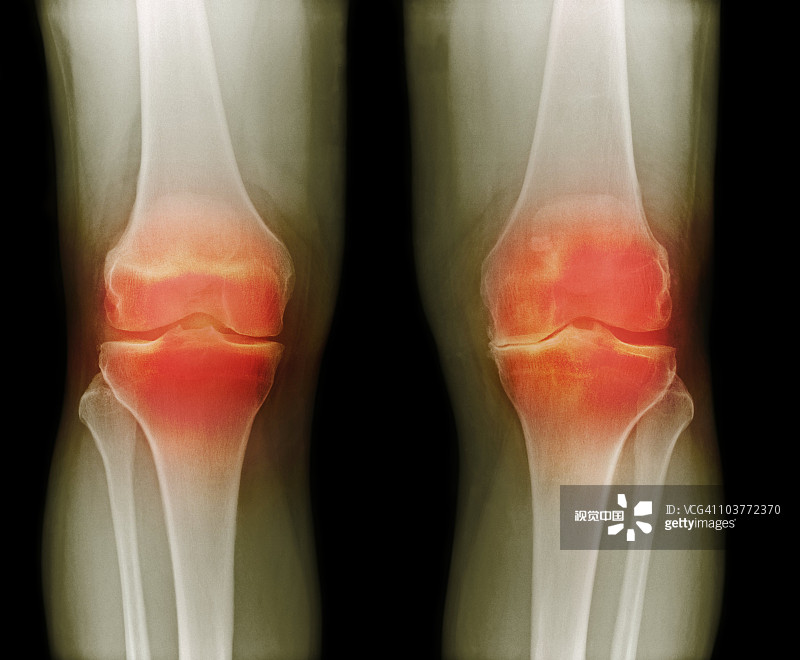

适应症:膝骨关节炎

贵医附院 | 人脐带间充质干细胞治疗膝骨关节炎患者的1期临床试验

- 2.依据参考中华医学会骨科学分会关节外科学组制定的“骨关节炎诊疗指南(2018年版)”,明确诊断为膝骨关节炎(KOA)

- 6.受试者研究侧膝关节Kellgren-Lawrence分级为II/III级。